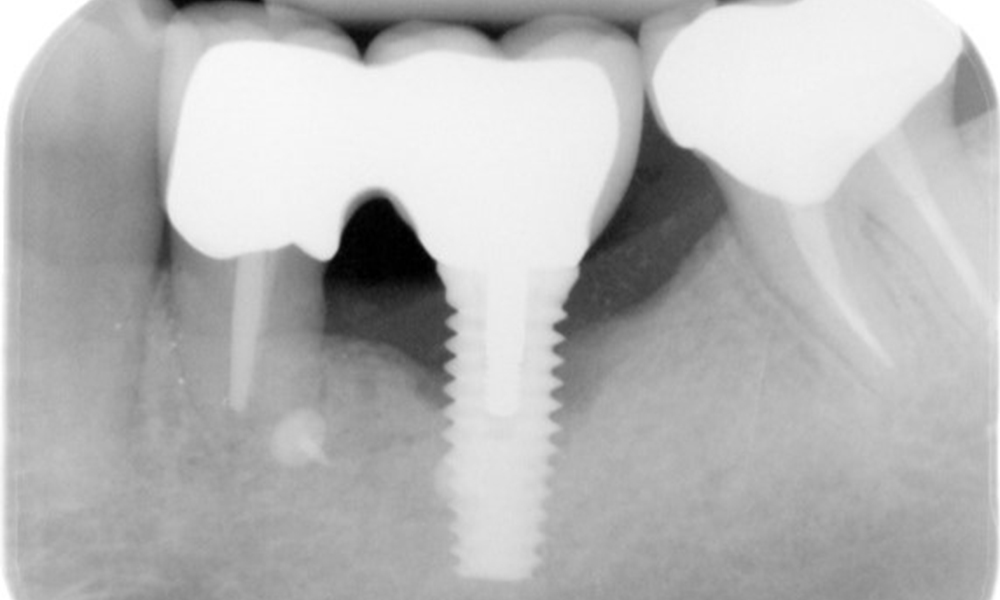

A 52-year-old patient presents at a preventive care session. The patient has no systemic disease and is not taking any medication. He has had various dental treatments and also has two active carious lesions. In addition, the patient has four implants (2nd, 3rd and 4th quadrants). He is revealed to have early periodontal disease (stage IV, grade B). His periodontal condition is stable; a probing depth of Probing depths (ST) of 5 mm is only evident at the implant in region 36. Gingivitis is also identified.

The X-ray images show the progression of bone loss.

The X-ray images show the progression of bone loss in the area of the implant in region 36: dental film from 11.02.2021 (left) and dental film from 18.01.2024 (right).